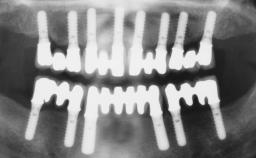

Fixed and removable prosthodontic implant therapy for restoration of the edentulous maxilla is both complex and challenging. Careful assessment and planning is needed in each individual case to explore whether a fixed or a removable solution will be the more suitable to satisfy the patient’s preference for optimal esthetics, phonetics, comfort and function. This Learning Pathway explores the prosthodontically driven treatment planning based on structured assessment, considered diagnosis and practical application in clinical case examples.

• recognize the importance of a prosthodontically driven plan and of planning implant configurations and placement accordingly

• describe the role of additional investigation by 3D reformatted scans in assisting treatment planning